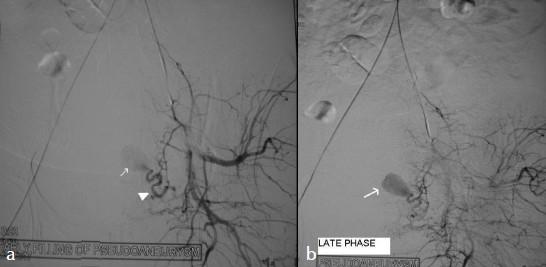

Uterine artery pseudoaneurysm is a rare cause of secondary postpartum hemorrhage but is potentially life-threatening and can occur after caesarean section (c-section) or a hysterectomy. A 28-year-old woman who developed secondary postpartum hemorrhage after c-section was diagnosed to have pseudoaneurysm from the left uterine artery on ultrasound (US) and computed tomography (CT) scan. She was treated with coiling of the pseudoaneurysm with stainless steel coil via selective catheterization of the uterine artery. The procedure was uneventful and the pseudoaneurysm was successfully obliterated. Angiographic embolization is a safe and effective method for treating postpartum hemorrhage due to pseudoaneurysm in hemodynamically stable patients. Therefore, it should be considered as a treatment option before resorting to surgery, in appropriately selected cases.

子宫动脉假性动脉瘤是继发性产后出血的罕见原因,但有潜在生命危险,可发生于剖宫产或子宫切除术后。一名28岁女性在剖宫产后发生继发性产后出血,经超声(US)和计算机断层扫描(CT)诊断为左子宫动脉假性动脉瘤。通过子宫动脉选择性插管,用不锈钢线圈对假性动脉瘤进行了栓塞治疗。手术过程顺利,假性动脉瘤成功闭塞。对于血流动力学稳定的患者,血管造影栓塞术是治疗假性动脉瘤所致产后出血的一种安全有效的方法。因此,在适当选择的病例中,在采取手术治疗之前应考虑将其作为一种治疗选择。